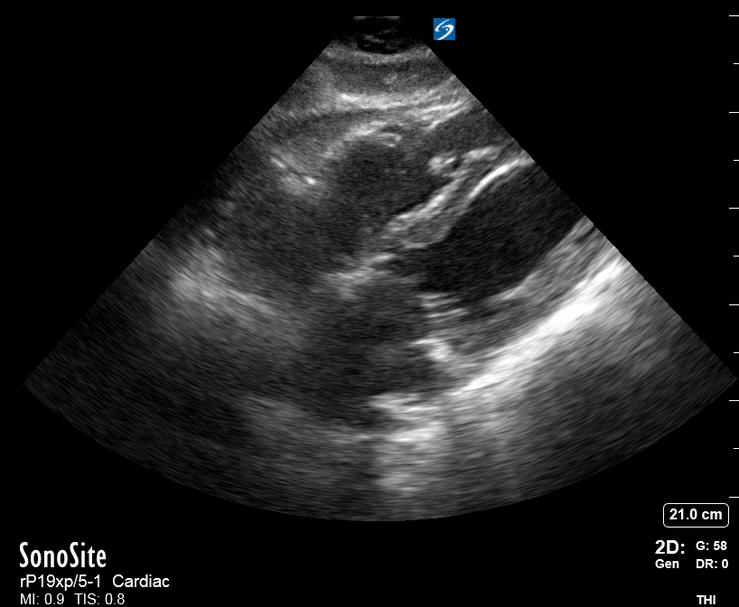

Effusion: is there a pericardial or pleural effusion?

Pericardial effusion is a continuum and can potentially evolve into haemodynamic collapse. Tamponade physiology is detectable earlier with ultrasound than with traditional physical examination, and it has been demonstrated that PoCUS improves mortality in penetrating cardiac trauma. Timely and accurate diagnosis is, therefore, vital.

THE VIEWS

The subxiphoid view is the most reliable for detecting pericardial effusion. Still, it is ideal to obtain different views not to miss a focal effusion as small amounts of fluid can lead to tamponade physiology. Tamponade does not link strictly to the size of the effusion, but correlates more with the speed of onset, causes, and haemodynamic effects.

PITFALLS & PLEURAL EFFUSIONS

A common error is to confuse a pericardial fat pad with effusion. Fatty tissue has a heterogeneous echotexture, moving in coordination with the myocardium, and it cannot be tracked around the heart, especially posteriorly and to the apex. Another pitfall is misinterpreting a pleural effusion as a pericardial effusion. However, they can be differentiated by their relationship to the descending aorta. Pericardial effusion may be seen between the aorta and the LV free wall, whereas pleural effusions are posterior to the descending aorta. Lastly, other causes, namely hypovolaemia and large pleural effusions, can cause RA and RV collapse.

CARDIAC TAMPONADE

Progressively rising pressure translates into evolving tamponade, and this accompanies a series of ultrasound findings:

Initially, the RA collapses during ventricular systole (closed AV valves).

Followed by RV collapse in ventricular diastole (open AV valves).

Ultimately leading to LV collapse.

In addition, the presence of a non-collapsible, plethoric IVC is one of the most sensitive signs of tamponade, and a finding easy to visualise. Conversely, a pericardial effusion in a haemodynamically stable patient with a collapsible IVC is unlikely to represent tamponade.